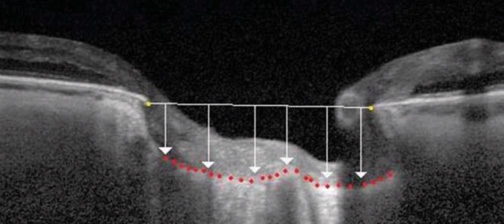

Figure 2. Anterior lamina cribrosa depth, shown by the red dotted line. The opening of Bruch membrane is located at the yellow dots on the horizontal white line.6

OCT provides high-resolution imaging of the layers of the retina, choroid, sclera, and ONH. It also gives information about the extent of RNFL loss near the ONH and the extent of ganglion cell layer loss in the macula. In addition to these well-known diagnostic analyses, it is now possible to locate and quantify the anterior lamina cribrosa depth (ALD) using spectral-domain OCT. The ALD is the deepest point below the opening of Bruch membrane (Figure 2), and it has been shown to correlate with the stage of glaucoma, change in IOP, visual field loss, race, and age.1-3